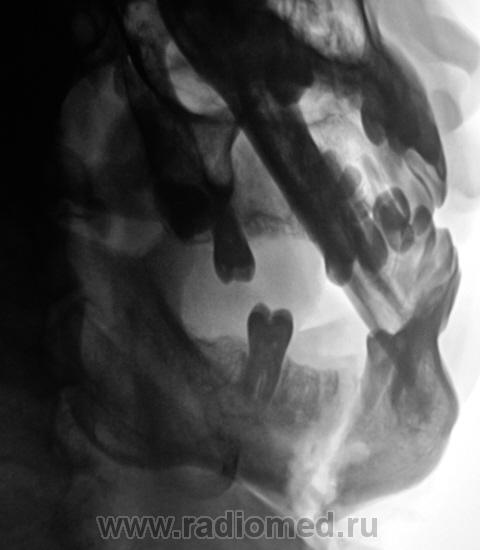

Пациент был направлен в рентгеновский кабинет для рентгенографии нижней челюсти 2 месяца тому с диагнозом "перелом нижней челюсти".

Произведены снимки.

Было высказано предположение о наличии "застарелого перелома" нижней челюсти и наличии остеомиелитического процесса. Пациент был направлен в областное челюстно-лицевое учреждение, где находился на стационарном лечении.